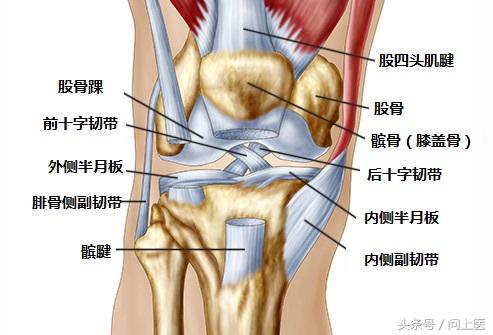

膝盖有很多运动部件,而且也经常被使用,所以出现问题的可能原因有很多。多次重复一种运动,尤其是如果没有循序渐进的过程,则可能会导致“过度使用”损伤。一些轻微的磨损和撕裂也会造成问题,尤其是年龄较大时。事故可能会导致骨折或组织撕裂,一些疾病也会使身体攻击自身关节。当膝关节出现问题时,及时就诊有助于医生诊断和治疗。

2. 十字韧带撕裂

这种情况通常发生在足球或篮球运动中,患者突然改变方向后就无法移动了,这可能是因为撕裂了膝盖后方的十字韧带。患者的膝盖会疼痛和肿胀,并感觉不稳定。

所有固定膝关节的组织都有可能被撕裂或拉伤,如连接骨骼与骨骼的韧带、连接骨骼与肌肉的肌腱。过度使用肌腱会导致肌腱炎。

8. 半月板撕裂

突然扭转或旋转时(尤其是膝盖承受全部重量时),就有可能会撕裂半月板(充当股骨和胫骨之间缓冲垫的弹性软骨)。前交叉韧带(ACL)的每一侧都有一个半月板。关节炎或年龄较大会提高半月板撕裂的风险。该疾病导致的疼痛定位不明确且难以描述,患者的膝盖可能会僵硬、肿胀、难以移动和伸展。